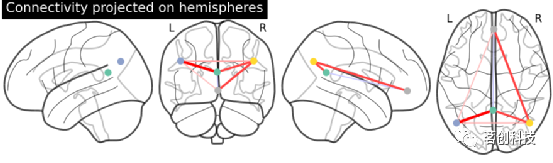

显示脑半球投射的连接体。注意(0,-52,18)包含在两个大脑半球中,因为x==0。

from nilearn import plotting

plotting.plot_connectome(partial_correlation_matrix, dmn_coords,

title="Default Mode Network Connectivity")